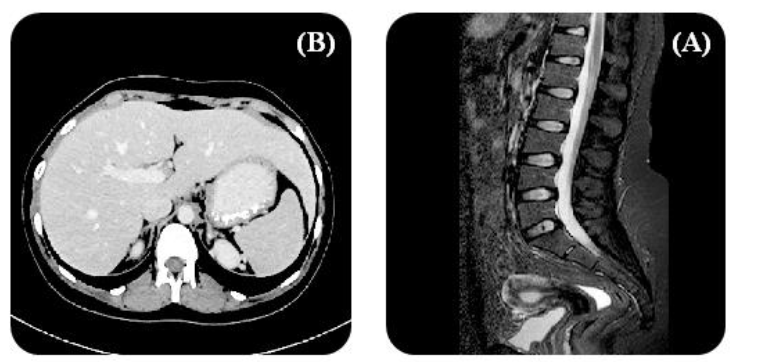

2. Pathophysiology of Neuroblastoma and Therapeutic Targets

A paediatric malignancy initiated from neural crest progenitor cells, exhibiting considerable heterogeneity that complicates treatment approaches, is termed neuroblastoma. Its pathophysiology is driven by genetic and epigenetic alterations, contributing to the tumour’s aggressive behaviour and resistance to conventional therapies. Because of the rapid progression and therapeutic resistance, high-risk neuroblastoma is commonly presented as abdominal masses that are related to poor prognosis. Some changes are demonstrated in the cellular plasticity in adrenergic (ADRN) and mesenchymal (MES) subtypes, showing responses to therapy and different immunotherapeutic target expressions. In neuroblastoma cases, no uniform genetic alteration is observed after sequencing DNA and RNA over 1000 times. This accounts for the complete spectrum of the disease.